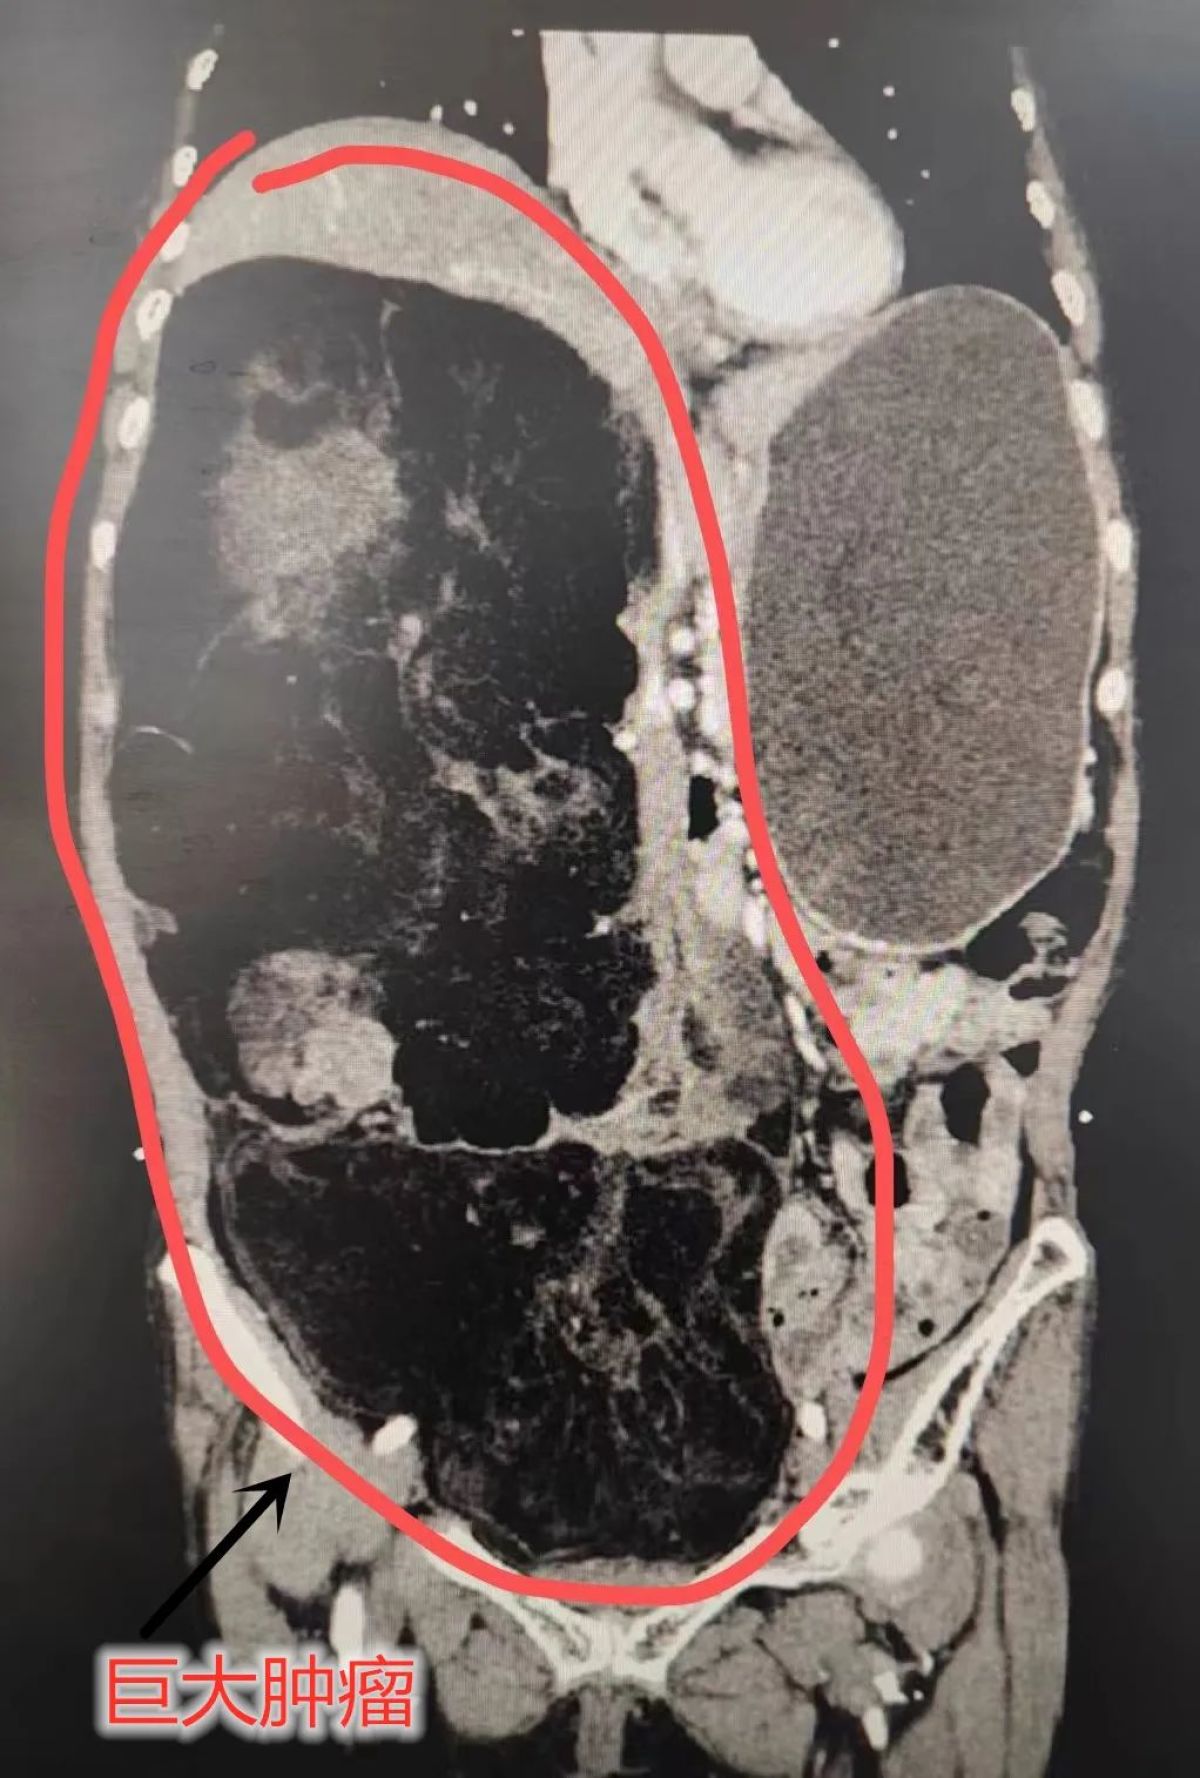

一罕见的腹部巨大肿瘤

图片尺寸1601x1203

术前ct检查提示,老人体内有巨大的腹膜后肿瘤.

图片尺寸762x688